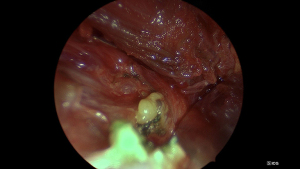

NIR was performed using the ICG rigid endoscope with Rubina camera head (Karl Storz, Tuttlingen, Germany). The endoscopic system utilizes a filter to switch between white light and NIR light emitted from a light-emitting diode (LED) source (Figures 1-3). The camera was used intermittently during key portions of the case to assist dissection and preservation of parathyroid tissue where in doubt, as well as for evaluation of the extracted thyroid specimen to identify any inadvertently removed parathyroid glands. Any identified glands were then reimplanted. The final specimen was then submitted to the same anatomical pathology laboratory for analysis.

Some studies evaluating the effectiveness of NIR have primarily used the technology to examine the extracted thyroid specimen for inadvertently removed parathyroids, thereby allowing the opportunity to reimplant (12,13). In our institution, we utilize the technology throughout the operation to assist in confirmation of parathyroid tissue in situ. We have found value in instances where parathyroid tissue may be difficult to differentiate from nodal tissue, fat, atypical thyroid nodular tissue or found in an intracapsular position. Figure 5 demonstrates visual contrast between fat and parathyroid tissue, allowing intra-operative differentiation. This may especially be useful in cancer cases where resection margins are paramount, as is removal of any suspicious extra-thyroidal tissue. The NIR camera is yet to be trialled as an adjunct in central neck dissection, but we anticipate it to be useful in improving efficiency and reducing inadvertent parathyroidectomy while maintaining oncologic outcome. If there is tissue suspected to be normal parathyroid in the central nodal compartment, use of the NIR camera would allow for quick identification and confirmation. This may minimize reliance on frozen section analysis and avoid the risk of retained disease or unnecessary parathyroid gland sacrifice when in close proximity to pathologic lymph nodes. In this study, of the 13 patients who underwent central neck dissection (all by naked eye detection only), there were seven cases of inadvertent parathyroidectomy. We believe that NIR may play an important role in balancing parathyroid preservation with thorough resection of malignancy.